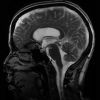

+13 +1Watch the brain jiggle with each heartbeat

With every heartbeat, fluid squishes through the brain and jiggles it like a bowl full of jelly. A new twist on magnetic resonance imaging illuminates these pulsing brain ripples, movements so subtle that they had escaped detection by current imaging technology. Abnormal brain motion could signal trouble, such as aneurysms or damage from a concussion.